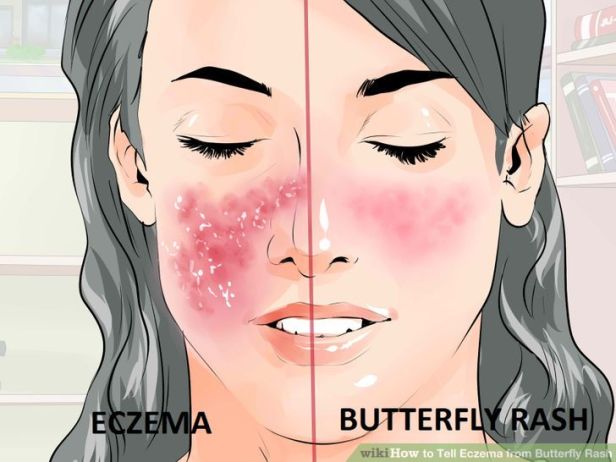

- Beberapa orang mengalami ruam merah dengan pola mirip jala (livedo reticularis).